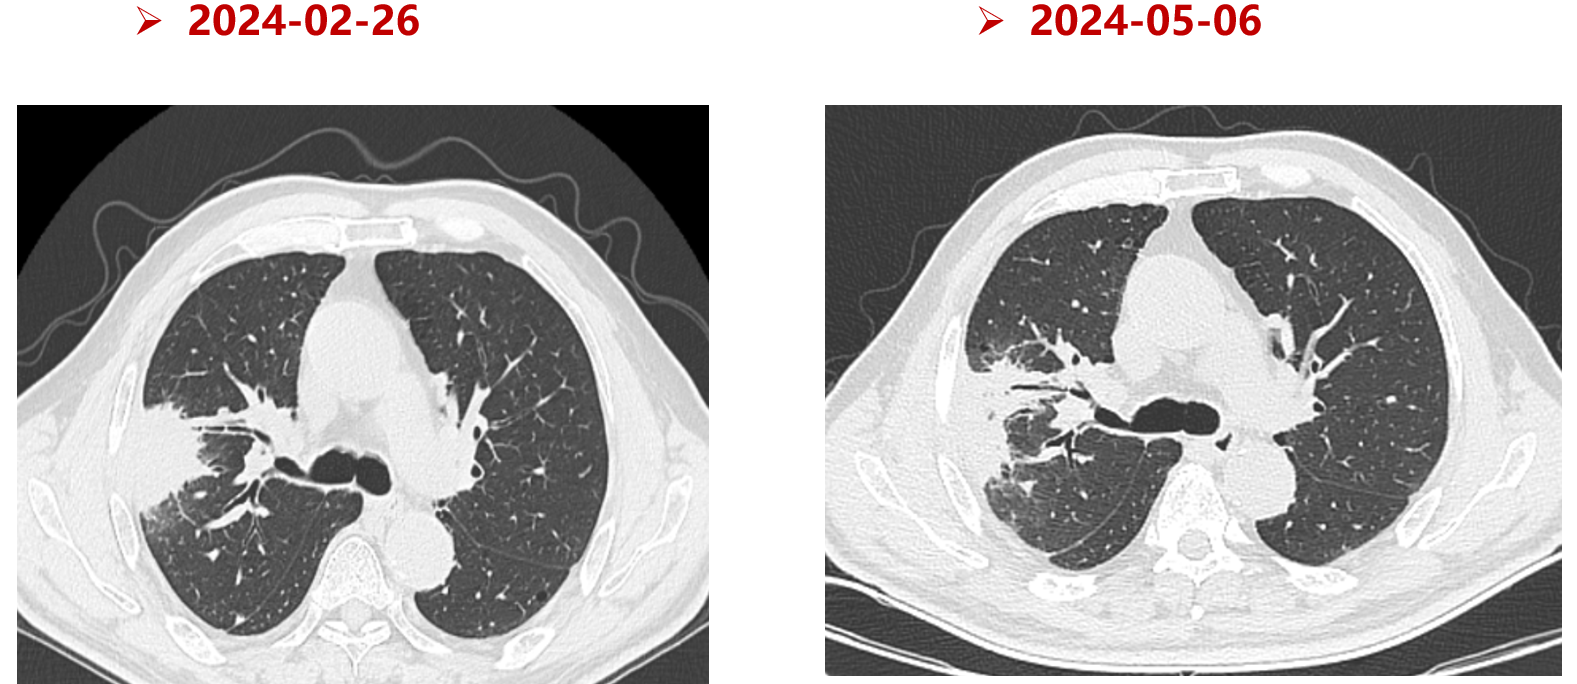

疗效评估:3周期治疗后复查CT,右肺病灶明显缩小,评估为部分缓解(PR),为手术创造了条件。

手术:2024年5月24日行“右肺上叶切除+纵隔淋巴结清扫术”。

术后病理:镜下见肺组织内多量炎症细胞浸润伴纤维化及局灶广泛坏死,未见存活肿瘤细胞。淋巴结(25枚)均未见癌转移。

病理分期:ypT0 ypN0 cM0。

疗效评价:病理学完全缓解(pCR)。